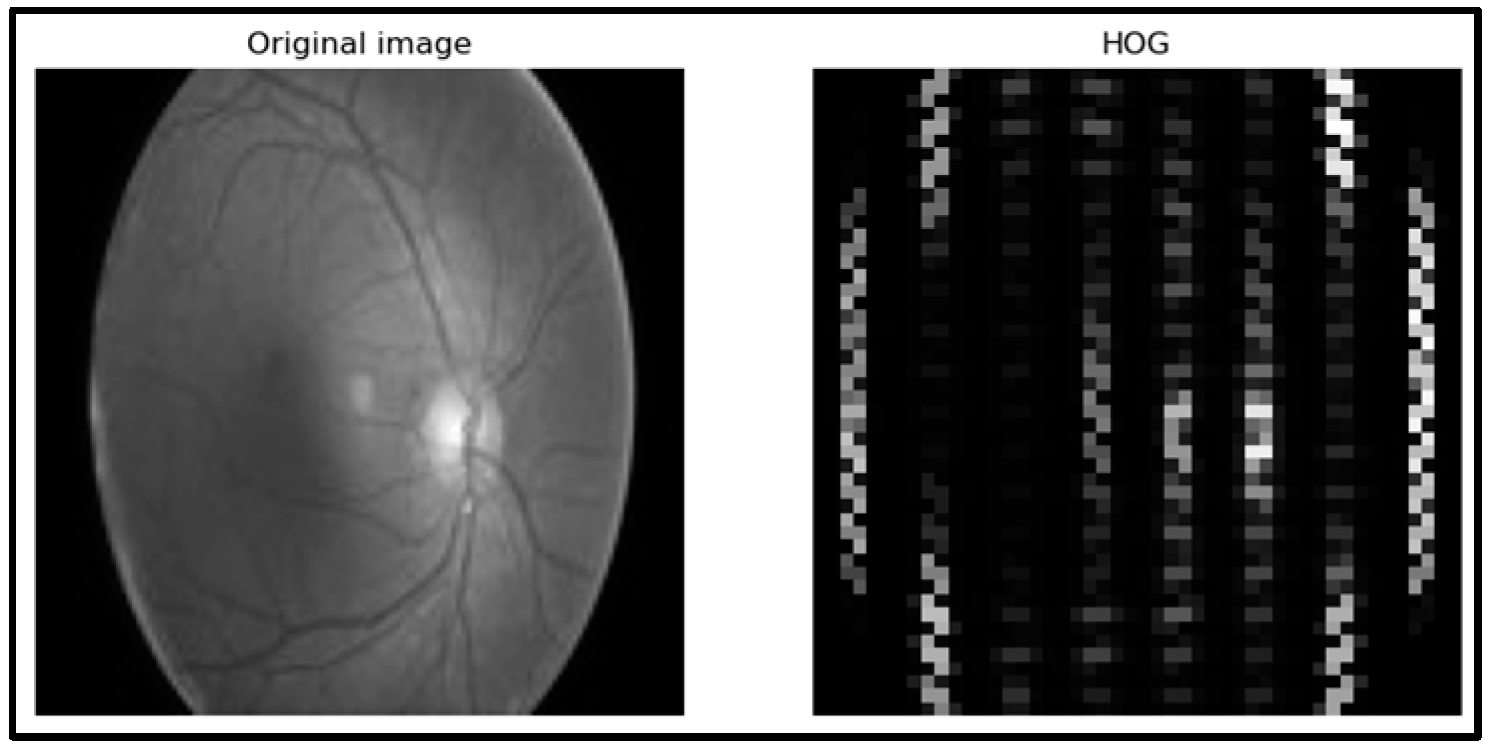

- HOG